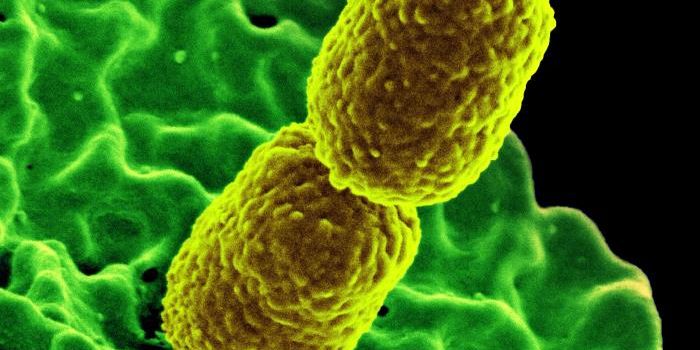

SEP 05, 2024Cell & Molecular BiologyCorynebacterium matruchotii ia a common bacterium that lives in human dental plaque; a colony is seen in this image by S ...

AUG 07, 2024Clinical & Molecular DXKlebsiella pneumoniae (K. pneumoniae) is a common Gram-negative bacterium. They can live almost anywhere, including wate ...